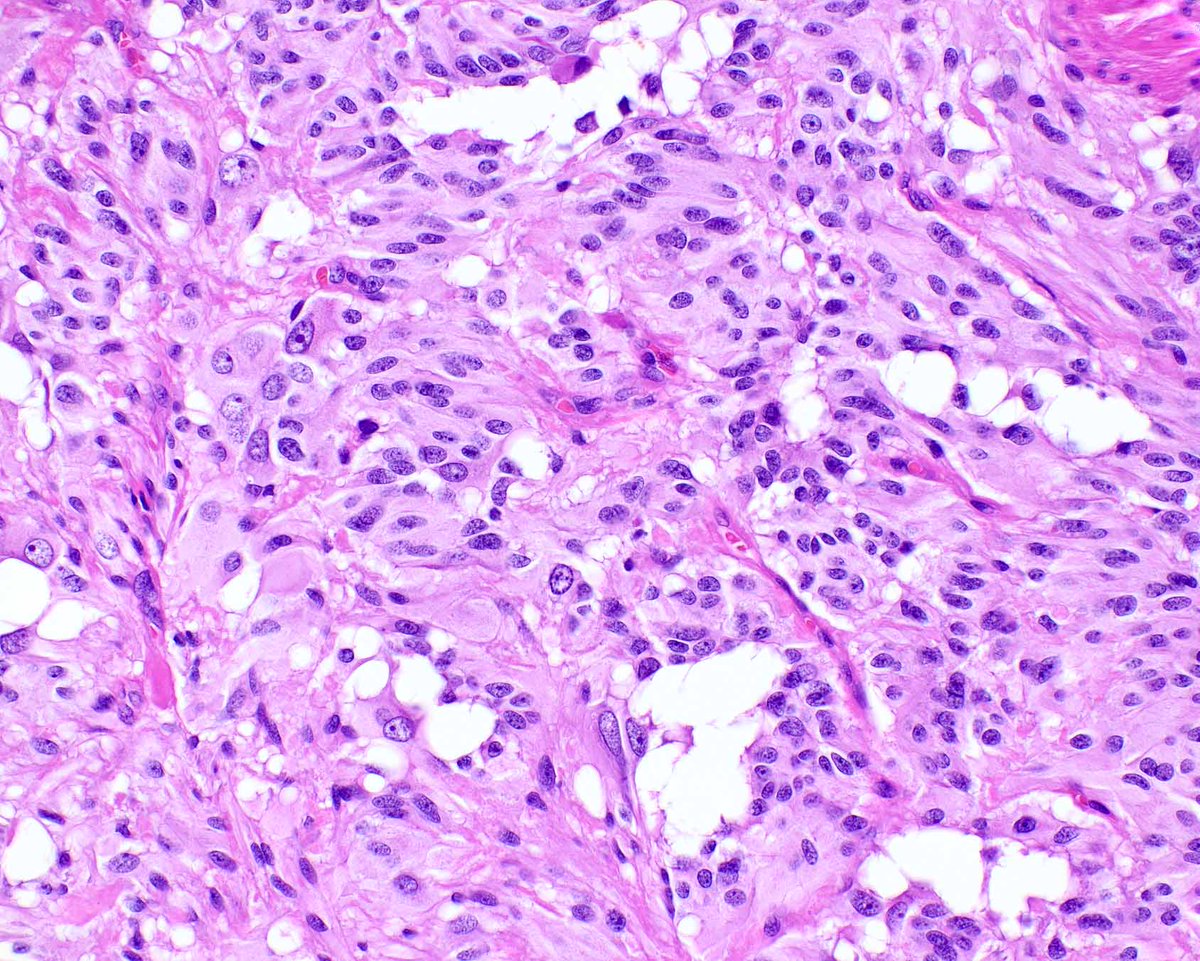

This atypical lipomatous tumor (well-differentiated liposarcoma) is unusual in containing plentiful lipoblasts.